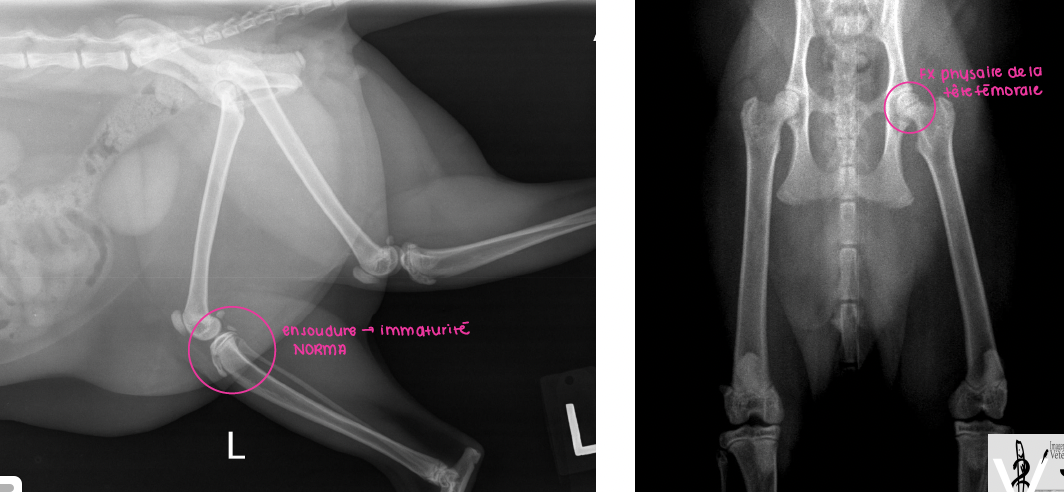

Cas 1: Ti-mine, un chat mâle castré de 10 mois est présenté pour une boiterie importante au MPG d’apparition aiguë

A. Je ne vois rien, donc ce doit être psychosomatique

B. Trauma au niveau des tissus mous

C. Avulsion de la tubérosité tibiale

D. J’hésite et je voudrais essayer une projection additionnelle

A